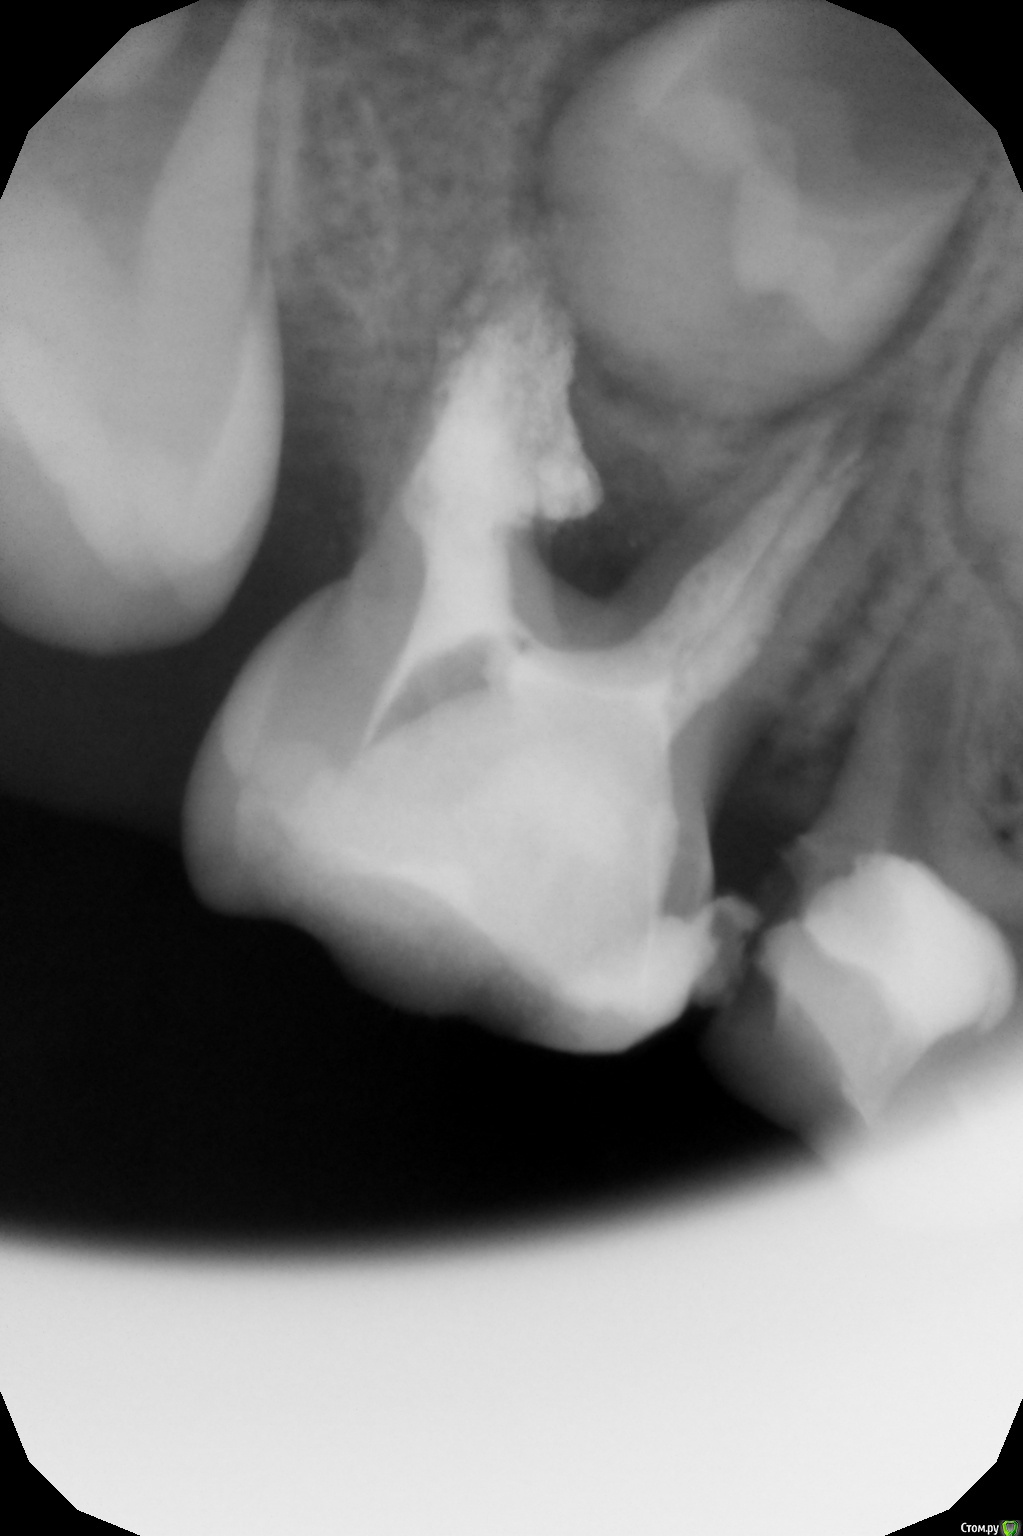

Джима Опубликовано 2 июня, 2016 Поделиться Опубликовано 2 июня, 2016 такая внутрянка потом вот так заканчивается:http://radikal.ru:8033/tempfiles/944645611b6245738098a3440436f518/-88693455.jpghttp://radikal.ru:8033/tempfiles/1f5a186b77424a42abc5b9ebf07dc18e/-88693455.jpgоставила тоже до прорезывания 4.6, там и коронки почти нет. Ссылка на комментарий

Джима Опубликовано 2 июня, 2016 Поделиться Опубликовано 2 июня, 2016 ну почему же полгода? ему отстоять год, а может, и полтора, пока 46 встанет в прикус. а вообще, думаю, если всё заживёт, можно его через месяца три-четыре короночкой покрыть - пожуёт ещё. у таких остатков проблема в разгерметизации пломбы: зуба почти нет, пломба огромна, как ни старайся, а через время всё равно протечёт и опять разрежение будет на снимке. а с коронкой не протечёт.здесь эвгенолкой пломбировала. метапекс уйдёт мгновенно. Кстати почему начальную резорбцию можно остановить и добиться заживления, а вот если пол корня рассосалось, то шансов нет? не совсем поняла вопрос? начальную внутреннюю резорбцию? Ссылка на комментарий

Джима Опубликовано 2 июня, 2016 Поделиться Опубликовано 2 июня, 2016 про ваш не знаю. там больно жидко метапекс в каналах выглядит, и кровило, говорите, сильно. вряд ли долго простоит. Света правильно написала, 36 выйдет - и на выход. Ещё раз напишу. Верхушечной резорбции в чистом виде у молочек практически не бывает. Резорбция идёт по фуркации с переходом на малую кривизну и до апекса - организм пытается съесть всё, что содержит воспалённую пульпу. Даже ещё не так: воспалённая пульпа, в т.ч. и в мелких канальцах в указанной зоне, работает как одно целое с воспалённым периодонтом в этой зоне. Вместе они съедают малую кривизну (забавно, что часто целым остаётся собственно апекс, бывает, что он полностью отделяется от корня). Наружная часть корня остаётся целой. А корневой канал становится срезанным по косой, с широченным выходным отверстием (назвать это апексом сложно). Чем больше эта дыра, тем быстрее вымывается материал из корневого канала. А пустоты в природе не бывает Мы используем активные силлеры - гидроокись кальция или ЦОЭ. Они не дают размножиться флоре. Нет силлера - есть флора, потому что говорить о 100% герметичных реставрациях в детстве не приходится: зубки мелкие, насыщенные органикой и одновременно хрупкие, с очень тонкими стенками. Поэтому наше лечение - это балансирование между плохими микробами в плохом зубе и хорошо проделанной работой в хорошем здоровом детском организме. Чем плотнее забита устьевая половина корня и чем надёжнее реставрация - тем выше шансы на успех у здорового ребёнка. 1 Ссылка на комментарий